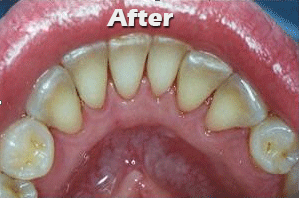

1. Scaling and polishing of teeth:

Scaling is done to remove the plaque and calculus accumulated around the teeth. This is necessary for the regular maintenance of a healthy dentition.

2)Flap surgeries (gum and bone surgeries):

Supportive bone around the root is diseased and partially destroyed.   First plaque and tartar are removed from the infected pocket.

The bone is smoothed & reshaped reducing spaces where bacteria can grow.   The gum is then attached back at or below the original gum line.